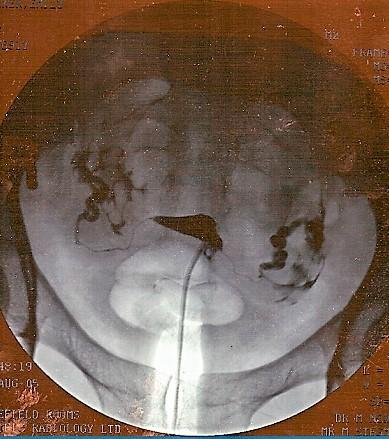

Dans l'image ci-dessous, le petit triangle noir au milieu est un utérus normal rempli de colorant. Le colorant entre par le tube qui se trouve à la base du triangle et va jusqu'au bord de la photo. Deux lignes très fines de colorant s'éloignent des pointes du triangle ; il s'agit de trompes de Fallope normales, remplies de colorant. Les plus grandes zones de colorant de chaque côté sont les endroits où le colorant a débordé des trompes normales.

Hystérosalpingogramme

Par jemsweb [CC BY-SA 2.0 (https://creativecommons.org/licenses/by-sa/2.0)], via Wikimedia Commons